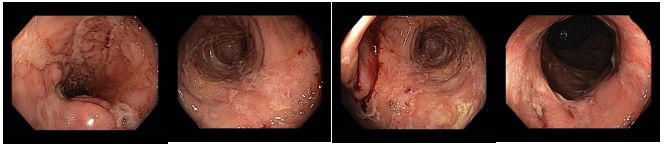

2022 klinická, laboratorní i endoskopická remise. Vysazen mesalazin

Koloskopie 2022/2: Pozánětlivé změny celého tračníku (jizvy), v rektosigmatu je reziduální ulcerace v centru serpiginózní ulcerace – bez makroskopických známek aktivity v tračníku i terminálním ileu. Vyšetření v bílém světle i NBI

Histologie: Chronické a fokálně výrazně aktivní zánětlivé změny v materiálu číslo IV., kde nález připouští diagnózu idiopatického střevního zánětu charakteru Crohnovy choroby s aktivitou

Popis případu dokumentuje dlouhodobou efektivní léčbu pacientky s crohnovskou kolitidou monoterapií vedolizumabem. Přestože se jedná o 4. linii léčby (2x anti TNF preparát, ustekinumab) původně velmi těžkého zánětu (plazivé ulcerace v rozsáhlých úsecích tračníku) bylo dosaženo klinické, laboratorní i endoskopické remise, která trvá již více než 5 let, nejsou patrné žádné nežádoucí účinky.